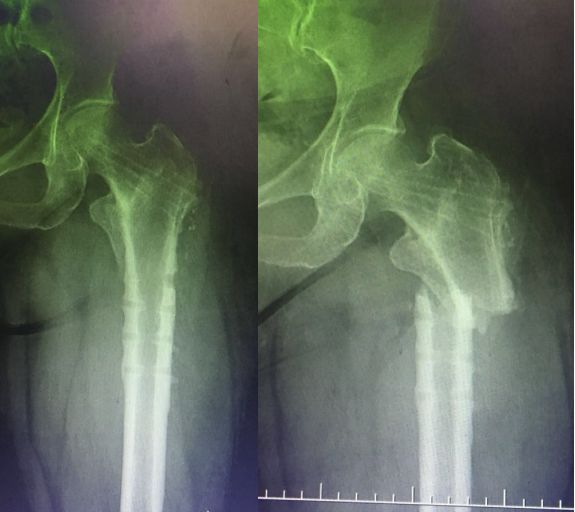

应力集中断裂。内固定过于坚强,钉子粗,钢板与过度处应力集中(没有必要手术,必须手术可以用随内针加石膏固定)。

应力集中,一旦断裂很难愈合。髋强直邻近骨折最好方法是关节置换,缓解应力集中同时做接骨手术

初次关节置换不好。功能差活动受限诱发进一步废用性疏松,应力集中

骨质疏松骨折选择钢板固定,应该是剥离过多骨坏死吸收。后大段异体骨移植吸收,最后失败难以收拾。开始用髓内钉会好些(理念问题)。不知道此病例结果如何?